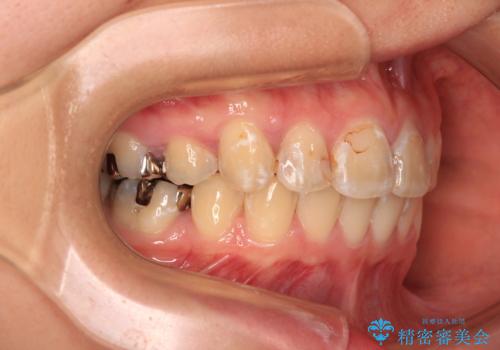

目立たないワイヤー装置にて抜歯矯正を行うこととしました。

下顎は過剰歯が埋伏しており、それが原因となってスペースが閉じなかったため、途中で抜歯して速やかに仕上げました。